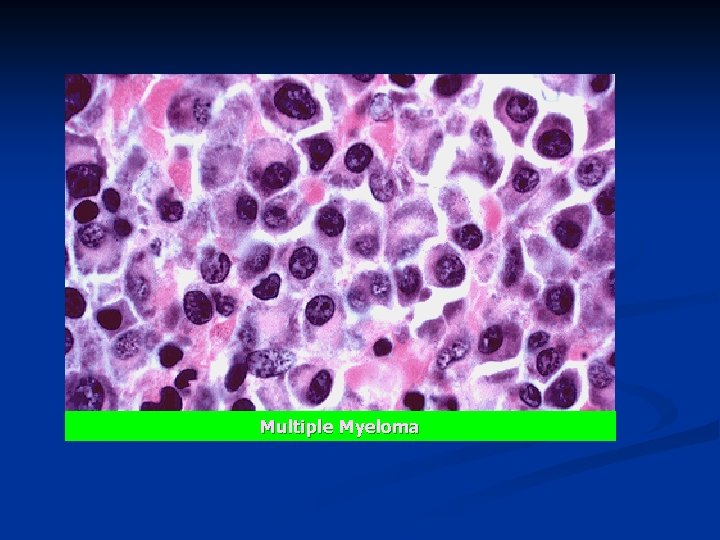

Microscopy: Bone marrow. n Plasma cell tumor: n n an eccentric, round, hyperchromatic nucleus sometimes with a "cartwheel" distribution of chromatin n frequent double or triple nuclei, n abundance of cytoplasm with a purple (basophilic) color and an occasional perinuclear "halo", n distinct cell borders.

Multiple Myeloma